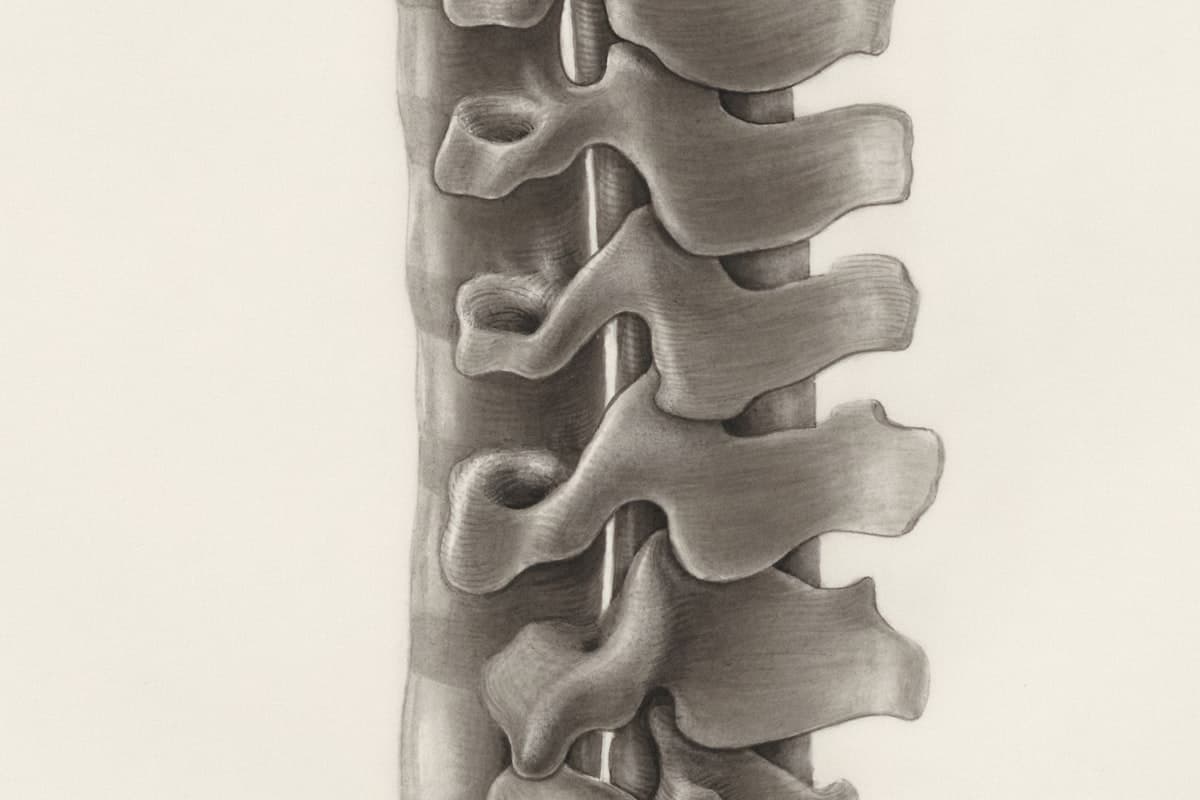

Neurosurgery

Brain, spine & peripheral nerves